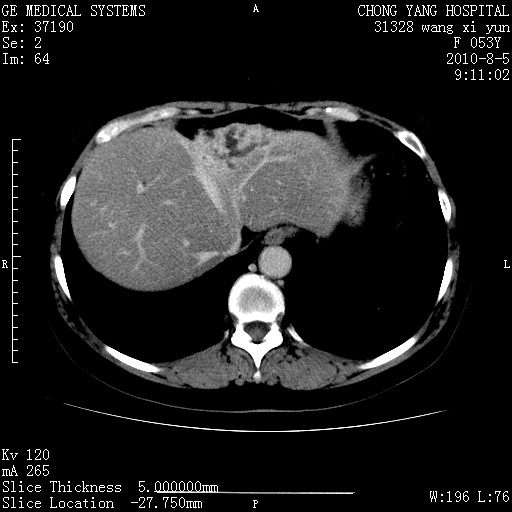

1)考虑肝左叶胆管细胞癌。2)脂肪肝。